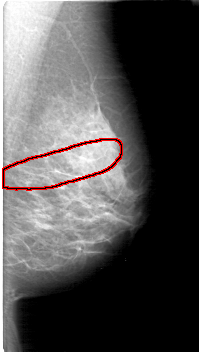

FILE: D_4052_1.RIGHT_MLO.OVERLAY

TOTAL_ABNORMALITIES 1

ABNORMALITY 1

LESION_TYPE CALCIFICATION TYPE AMORPHOUS DISTRIBUTION SEGMENTAL

ASSESSMENT 0

SUBTLETY 3

PATHOLOGY BENIGN

TOTAL_OUTLINES 1

BOUNDARY